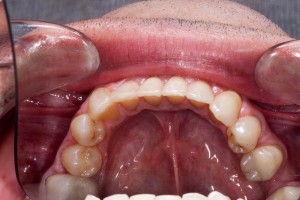

this treatment uses the best of all modern techniques, traditional train track braces with metal wires and metal brackets are very functional and work exceptionally well, however many patients dislike their cosmetic appeal. Six Month Smiles takes the functional aspect of these braces and applies a modern twist (pardon the pun) by providing clear brackets and tooth coloured wires to ensure that the treatment is barely noticeable.

- Trademarked Six Month Smiles clear brackets and tooth coloured wires to ensure your orthodontics is almost invisible.